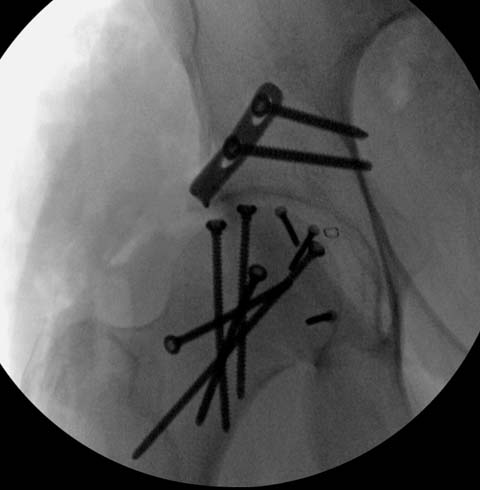

Здесь клинические примеры: Первый случай передний доступ, второй с ICP

monitor Flipp Trochanteris

и с переломом заднего края.